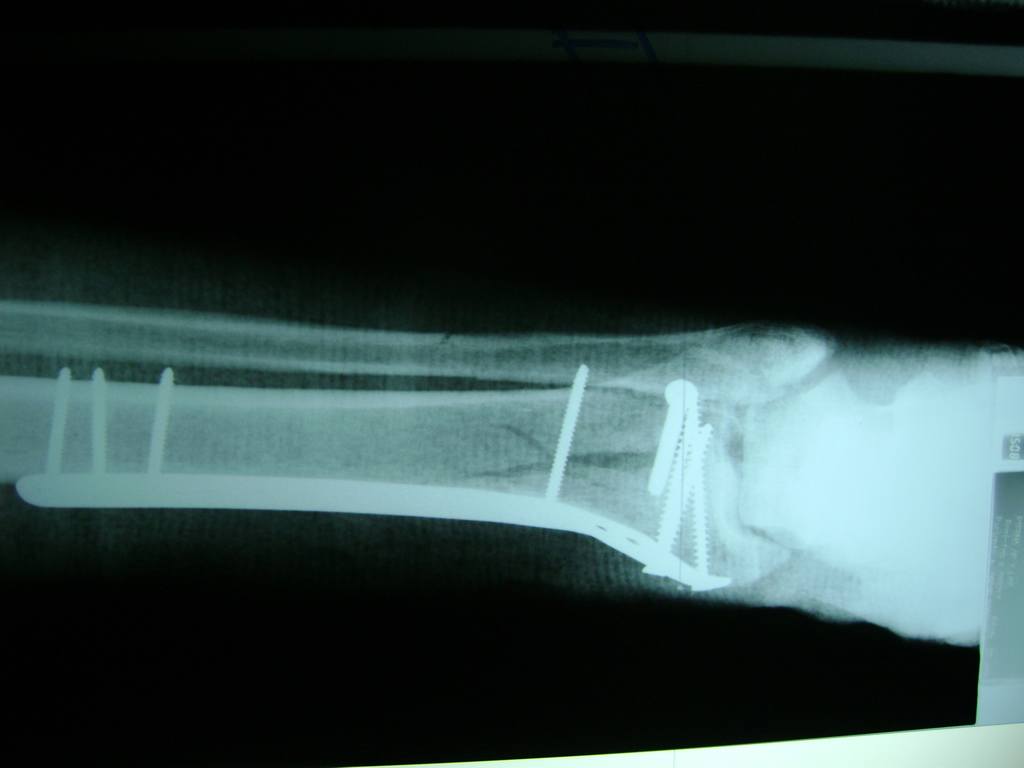

Cirugías de Peroné y Tibia

Aunque cada uno de estos huesos puede fracturarse por separado, normalmente la rotura es una lesión que se produce de forma conjunta

La mayor parte de las roturas implican a la parte proximal del hueso (parte del hueso próximo a la rodilla) o a la parte distal (parte del hueso cerca del tobillo).

Debido a la fina cobertura de piel que recubre la tibia y el peroné, las fracturas generalmente son abiertas, es decir, el hueso roto rasga la piel, atravesándola. Las fracturas de tibia y peroné generalmente se producen por un fuerte impacto o torsión.